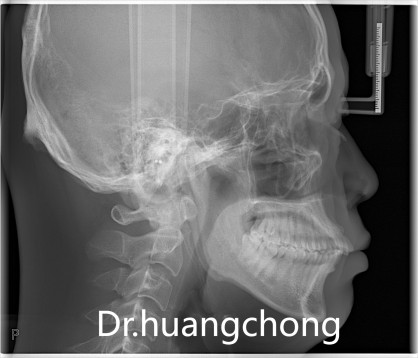

医生检查发现:李先生的上颌门牙中有一颗多生牙,上前牙唇倾度较大,牙龈退缩。结合临床表现与影像学检查,诊断为:1. 上颌多生牙;2. 慢性牙周炎;3. 牙列不齐。

李先生的正畸治疗计划为:拔除多生牙及片切牙齿来创造空间排齐内收前牙。拔除多生牙后获得了一部分间隙,但这还不足以使得门牙完全内收,因此还需通过片切牙齿再次创造间隙,将上前牙尽量内收。同时,由于片切,使得邻接面积加大,邻面触点根向移动,也可以减轻牙周病患者正畸后必然会出现的“黑三角”问题。

对于这种上颌前突的病例,内收前牙是改善侧貌的关键。但“内收空间”从何而来、如何使用,直接关系到上述黑三角和牙根及骨吸收问题的发生。

术前术后对比照